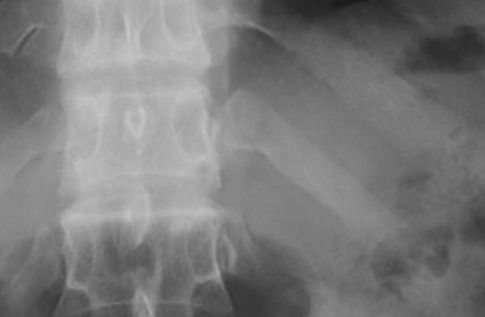

自分の肘が脇腹に入り余りの痛さに病院へ→レントゲン撮ると肋骨ちょびっと骨折だった。